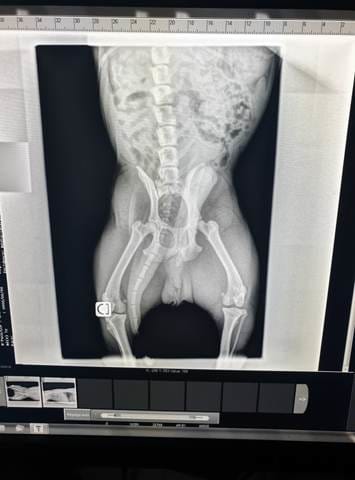

je suis allez chez le vétérinaire (j'ais payer mon loyer pour une radio mais bon quand on aime on ne compte pas :) le vétérinaire ma dit que c’était une sorte de malformation héréditaire sans être précis du tout .. et qu'il fallais attendre pour voir, du coup 5 mois plus tard ça ne fait qu'empiré , j"ai gardé les photo de la radio

Quand pensez vous ?